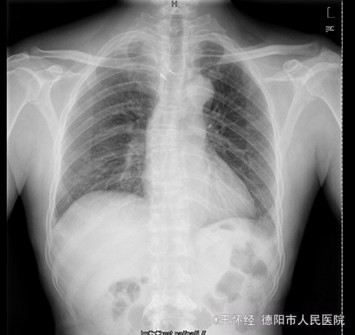

患者男,52岁,因“车祸伤后右肩部、右胸壁疼痛伴右上肢活动障碍1+天”入院。入院1+天前,患者因车祸伤致右肩部疼痛、有胸壁疼痛、右上肢活动障碍、无法上抬,无明显麻木,右胸锁关节处可见一明显隆起硬块、压痛明显,同时自觉少许呼吸困难,我院急诊行X光片示“右胸锁关节脱位”,遂收住我科。

查体:右侧胸锁关节处叩压痛明显,可扪及一隆起、质硬,右侧胸壁乳头周围肿胀,右肩外展因胸锁关节处疼痛而受限受限。 辅查:X片及CT提示示右侧胸锁关节向前脱位、双侧第一肋骨骨折

初步诊断:车祸伤:1.右侧胸锁关节前脱位;2.双侧第一肋骨骨折。 诊疗计划:右侧胸锁关节脱位切开复位,锚定固定修复关节囊及周围韧带。